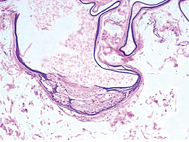

患者,男,25岁,发现躯干部有囊性结节7年于2015年9月11日在本院就诊。患者7年前入伍后洗澡时无意间发现胸部有数个绿豆大囊性结节,无自觉症状,尔后皮疹逐渐增大增多,并蔓延至腹部。患者平素体健,家族中未发现类似疾病患者。体格检查:一般情况可,心、肺、腹部等系统查体未见异常。皮肤科专科检查:胸腹部见大量粟粒至黄豆大圆形或类圆形、皮色或淡黄色的囊肿,无自觉症状(图1)。组织病理学检查结果:囊肿位于真皮,有上皮围绕,囊壁由鳞状上皮组成,囊壁内可见皮脂腺小叶,囊腔内容物为皮脂、少许角质物及毛干。诊断为单纯性多发性脂囊瘤(图2)。未予以治疗。